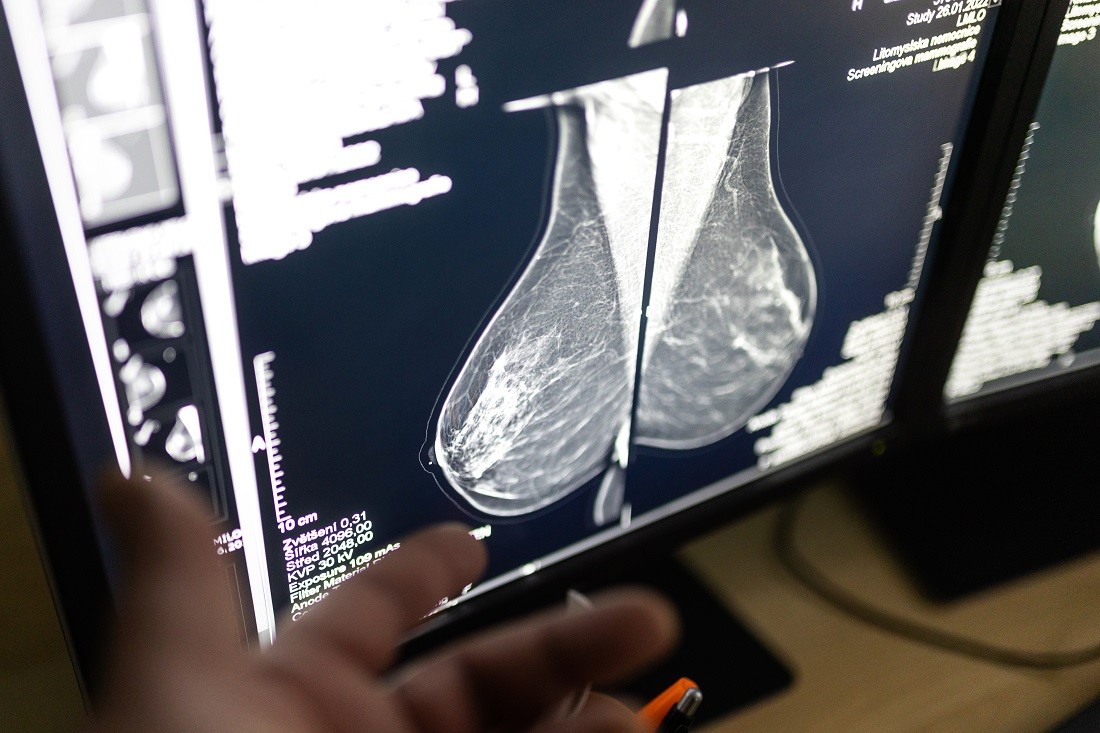

Mamodiagnostické pracoviště Svitavské nemocnice se jako každý rok zapojilo do projektu Ženy ženám. V rámci této akce mohou ženy, které nemají nárok na proplacení vyšetření pojišťovnou, absolvovat ultrazvukové nebo mamografické vyšetření prsou o 200 korun levněji.